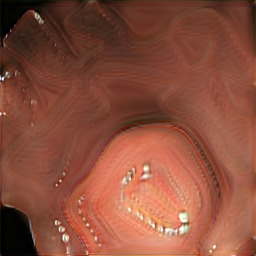

In Fig 7, we provide a visual comparison between pure generated synthetic images and style transferred images ( = ). Samples with the style transfer ratio are not depicted here because it is difficult to see the differences visually. The first column of Fig 7 shows the real images used as content images to transfer styles. The rest of the images in the first row of each image shows synthetic images generated from SinGAN-Seg before applying the style transferring algorithm. Then, the images in the second row in the figure show the style transferred synthetic images. Differences of the synthetic images before and after applying the style transfer method can be easily recognized from images of the second reference image (using and rows in Fig 7).